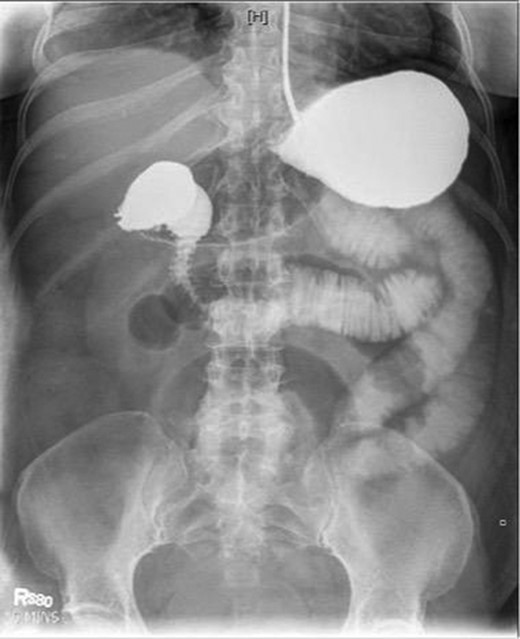

Laboratory studies were remarkable for leukocytosis, and an elevated lactate that improved with hydration (Fig. 1), while urinalysis was unremarkable. Abdominal CT scan obtained at this time demonstrated a partial SBO in the mid-small bowel as well as inflammation and thickening of the duodenum. A small bowel series was ordered, and showed high grade SBO (Figs 2–5).

Fluoroscopic barium study demonstrating oral contrast agent progression through the small bowel at 1 h after ingestion. The stomach is distended, with dilated bowel loops throughout the abdomen.